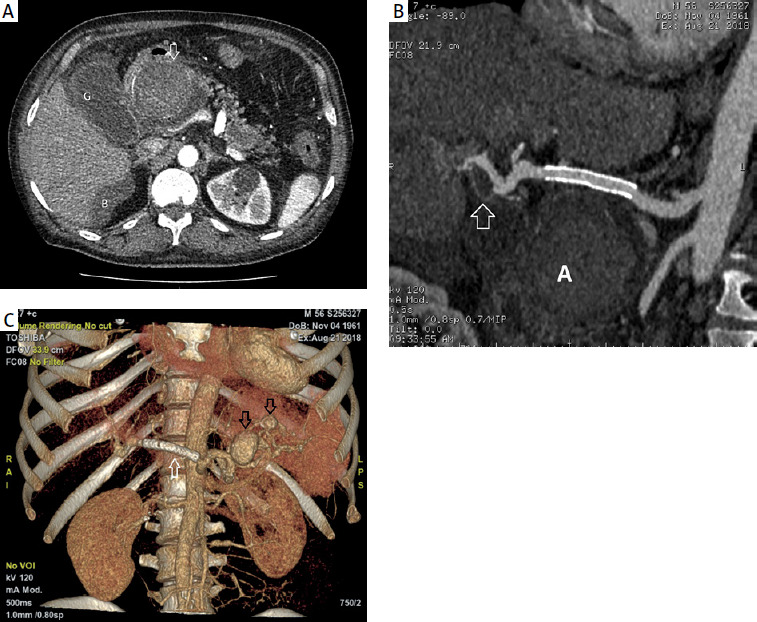

Figure 2

A – CT image after the applied treatment (angiographic phase, acquisition about 20 s after intravenous injection of contrast agent, intra-abdominal region) showing a large aneurysm, located along the course of the common hepatic artery, with no streaking of contrast into the sac (white arrow). The gallbladder is visible laterally (G). There is persistent fluid around the liver (B). B – CT image after treatment (angiographic phase, curved reconstruction along the common hepatic artery and hepatic artery) showing the implanted stent graft and the aneurysm located along the course of the common hepatic artery without contrast streaking into the pouch (A). Distally from the stent graft, an aneurysm with a small wall defect is visible along the course of the hepatic artery (white arrow). C – Arterial phase CT image – 3D reconstruction shows implanted stent graft (white arrow), aneurysm along the course of the common hepatic artery without contrast streaking into the sac (A). Along the course of the tortuous splenic artery, 2 aneurysms are visible (black arrows)